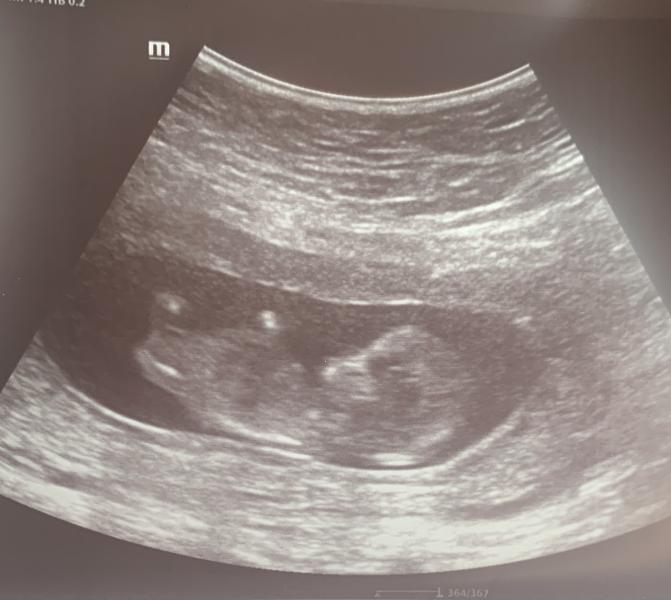

Ну вот и пройден 1 скрининг. Все хорошо!!! КТР 6 см, ТВП 1,1 мм, носовая кость 1,9 мм (все соответствует сроку)

Малыш сначала недовольно дрыгал ножками (разбудили), потом взял кулачок в ротик и повернувшись на бочок,продолжив спать. Так интересно, совсем маленький комочек, но уже человечек!!!!😊💛

У нас тоже сегодня 1 скрининг был🙂